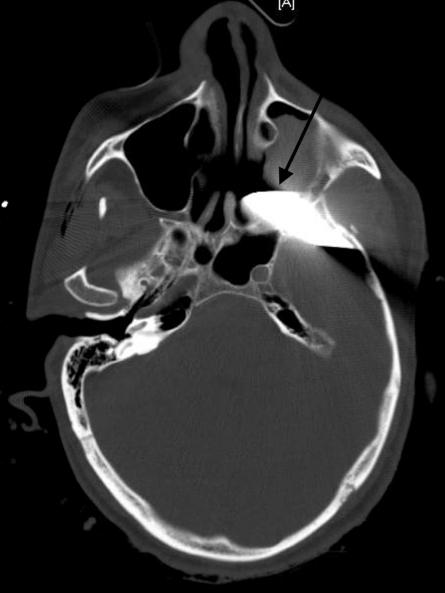

显示刀穿透左侧颞骨,左侧蝶骨,左侧翼腭窝和左侧上颌窦(图1,2,3)

图片尺寸445x593